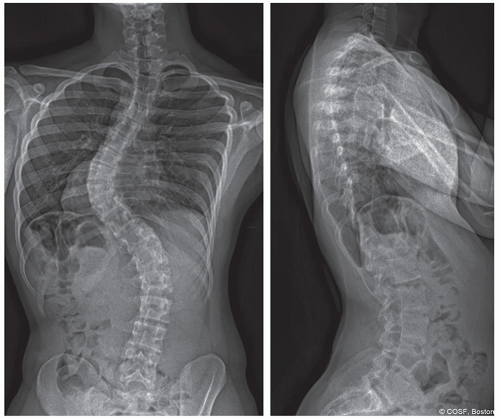

Atypical curves: Left thoracic, kyphosis, severe coronal decompensation

Additional preoperative imaging is required and should include magnetic resonance imaging (MRI) of the entire spine to evaluate for neurologic anomaly, specifically tethered spinal cord, Chiari malformation, and syrinx (Figure 3.3)